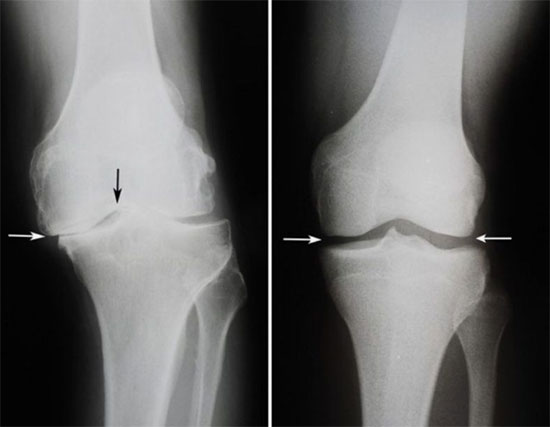

Después del curso de Flexosamine las articulaciones se recuperaron completamente